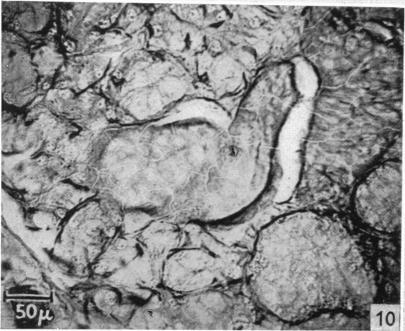

The silver staining of myoepithelial cells, particularly in the mammary gland, and their relation to the ejection of milk.

J Anat. 1952 Jan;86(1):49-57.